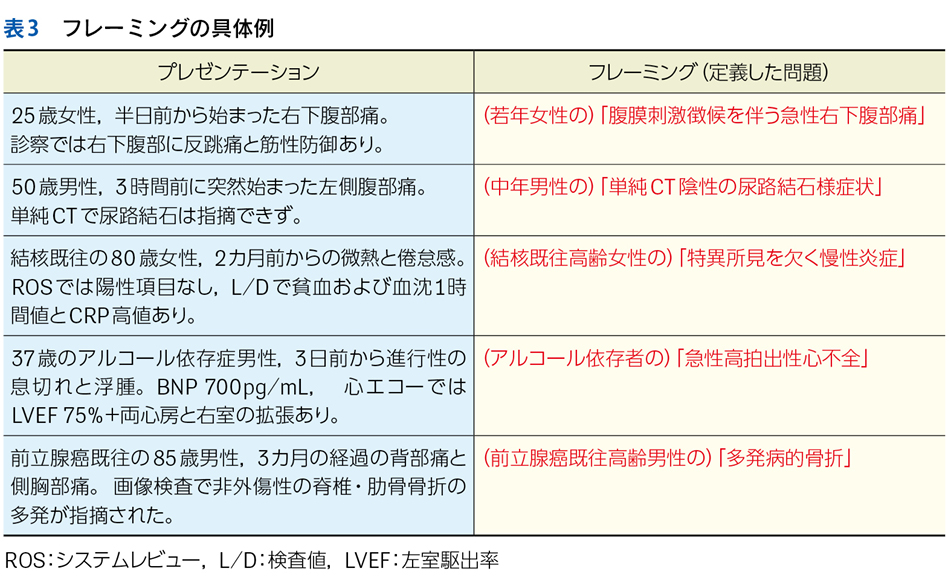

▶ 表3にフレーミングの例をいくつか示す。